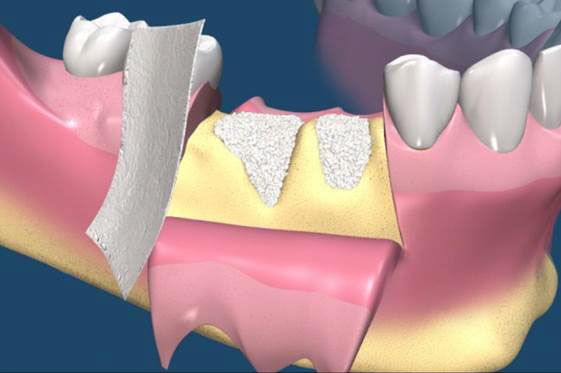

骨粉合併再生膜

在 GTR 及 GBR 技術中所使用的阻隔膜是用來將缺損的區域分開成兩個隔間。 GTR 技術的目的是再生完全俱功能的牙周膜,包含新的牙骨質、牙周韌帶(PDL)及新骨。GBR 技術的目的是再生新骨,對此,細胞從下層的骨組織需要分佈至缺損處。(圖09-12)